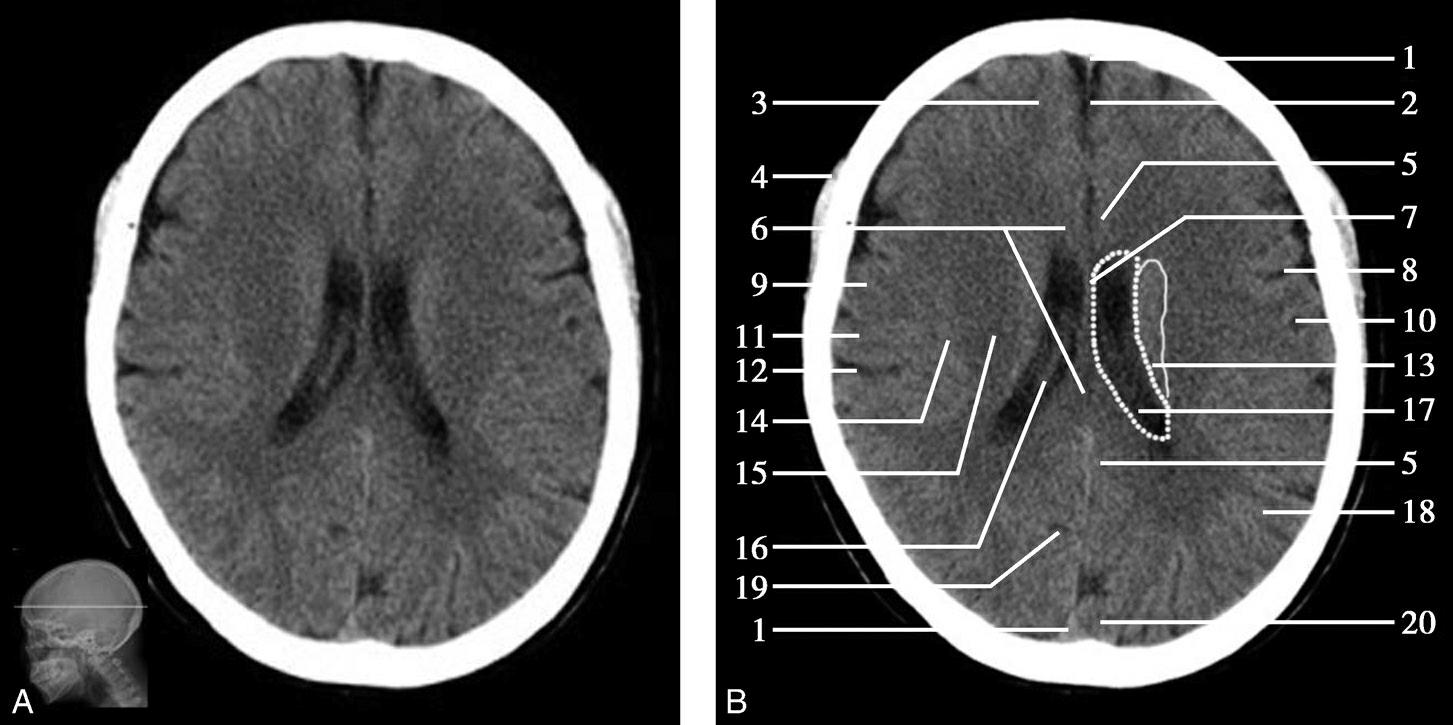

图1-2-21 中脑导水管层面

A.横断面;B.横断面标注

1.额窦;2.上矢状窦;3.大脑镰;4.额叶;5.颞肌;6.外侧裂;7.岛叶;8.尾状核头;9.外囊;10.第三脑室;11.豆状核;12.颞叶;13.中脑;14.中脑导水管;15.环池;16.四叠体池;17.小脑上蚓部;18.枕叶

图1-2-22 中脑导水管层面(骨窗)

1.额骨;2.蝶骨大翼;3.蝶鳞缝;4.颞骨;5.顶骨;6.顶枕缝;7.枕骨

中脑位居此层面的中央,其腹侧可见两侧大脑脚,大脑脚底有黑质与红核,中脑背侧可见左右稍隆起者为上丘,上丘后方为四叠体池,中脑顶盖的前方可见中脑导水管断面呈针孔样,中脑外侧为环池,中脑前方中间为第三脑室下部。第三脑室下部两前外侧有尾状核头及豆状核壳部,尾状核头及壳核部分相连,壳核的外侧为屏状核、岛叶及外侧裂池,再外侧为颞盖,其前部为颞上回,后部为颞中回。外侧裂池分隔前方的额叶和后方的颞叶,可作为区分额叶与颞叶的重要标志。四叠体池后方有小脑上蚓及两侧呈倒“八”字形的小脑天幕,天幕后方为直窦和上矢状窦。